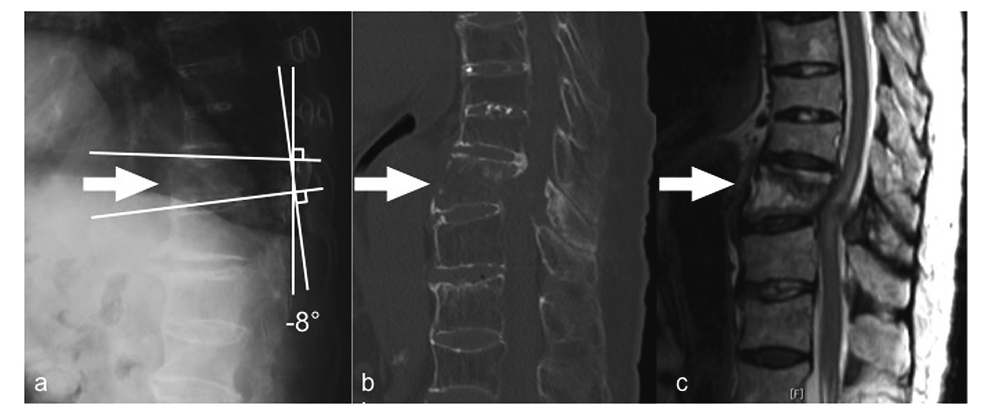

An 86-year-old woman with no significant past medical history presented with acute back pain after a fall and was transferred to her local hospital. Plain radiographs showed a bone bridge spanning more than four intervertebral bodies without a narrow intervertebral space (Figure 1a, b). Magnetic resonance imaging (MRI) showed a Th10 fracture (Figure 1c). She was diagnosed as having DISH and a Th10 fracture. She underwent conservative treatment because of her extreme age and no clear instability. She started gait exercise at 2 weeks after injury with immobilization by a rigid orthosis. Twenty-five days after injury, she presented with bilateral leg paralysis and numbness. Since delayed paraplegia was suspected, she was transferred to our hospital for surgical treatment. On admission, she had bilateral leg paralysis (grade 3 on manual muscle testing: MMT) below the iliopsoas and hypoesthesia of the anterior thighs. She had no bladder or bowel dysfunction. A lateral plain radiograph showed a decreased local kyphotic angle (Figure 2a). Computed tomography (CT) showed anterior expansion with a bone defect in the Th10 vertebral body and subsequent decreased kyphosis due to distraction-extension injury (reverse Chance fracture) (Figure 2b) and ossification of the ligamentum flavum at bilateral T10/11. MRI showed an intramedullary high-intensity area on T2-weighted images (Figure 2c), indicating instability and non-union at the same level. She underwent surgery 50 days after the injury. Laminectomy of Th10, partial laminotomy of Th11, Th7-L1 posterior fusion with pedicle screws and additional stabilization with laminar hooks to Th6 and L1 laminae to avoid back out of the screws, Th9-11 anterior fusion with a plate, and autologous bone grafting were performed simultaneously (Figure 3). In situ fusion in the prone position was done with no alignment correction. After surgery, her paralysis improved, and she started gait exercise with no limitation. Eight days after surgery, she presented with low back pain and paralysis (grade 2 on MMT) in her legs with no apparent cause. CT revealed an L1 fracture in the middle of the vertebral body, which was the caudal end of the fusion (Figure 4b). The patient refused further surgical treatment and werewas transferred back to the previousinitial hospital. She was bedridden thereafter because of the pain, and theher paralysis did not improve. Finally, shethe patient was die of pneumonia 4 month after surgery.

a, Lateral plain radiograph before surgery showing a decreased local kyphotic angle. b, Computed tomography (CT) before surgery showing anterior expansion with a bone defect in the ventral Th10 vertebral body and subsequent alignment change due to distraction-extension injury. c, T2-weighted MRI before surgery showing a bone defect at the ventral L10 vertebral body and an intramedullary high-intensity area at the Th10 level.

The present case showed a fracture at the caudal end of the fusion in the early stage after surgery. To date, no cases involving postoperative fractures after fusion for vertebral fractures with DISH have been reported. Inappropriate postoperative alignment may have been the reason for this fracture. It has been reported that patients with DISH have rigidity of the spine and kyphotic change15). Thus, the ability of spinal alignment to change and compensate would have been poor in this patient. The local kyphotic angle was 2° at the initial visit; however, when delayed paraplegia occurred, the angle was decreased to -8°. Finally, it was not corrected surgically, and it decreased to -11° (Figure 3). The decreased kyphosis could have caused a subsequent horizontal shear force to L1 when the patient sat on the bed and when she walked.